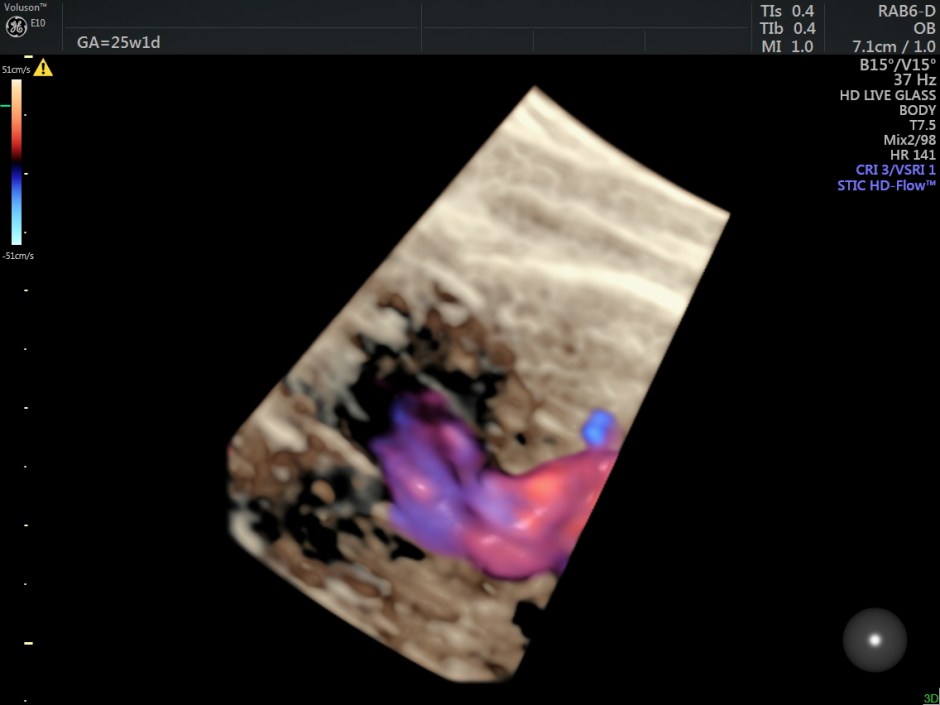

The following are some reconstructions.

This fetus showed left heart dysplasia, a small VSD and Double Outlet Right Ventricle with malposition of the great arteries.